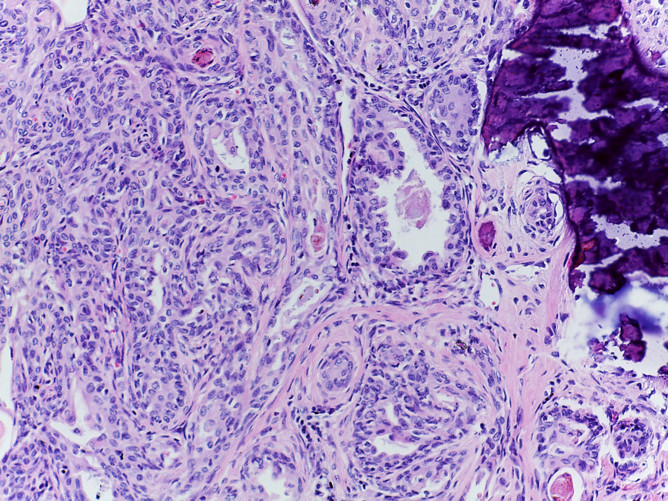

Tumor de células fusiformes con diferenciación semejante a timo (SETTLE por sus siglas en inglés).